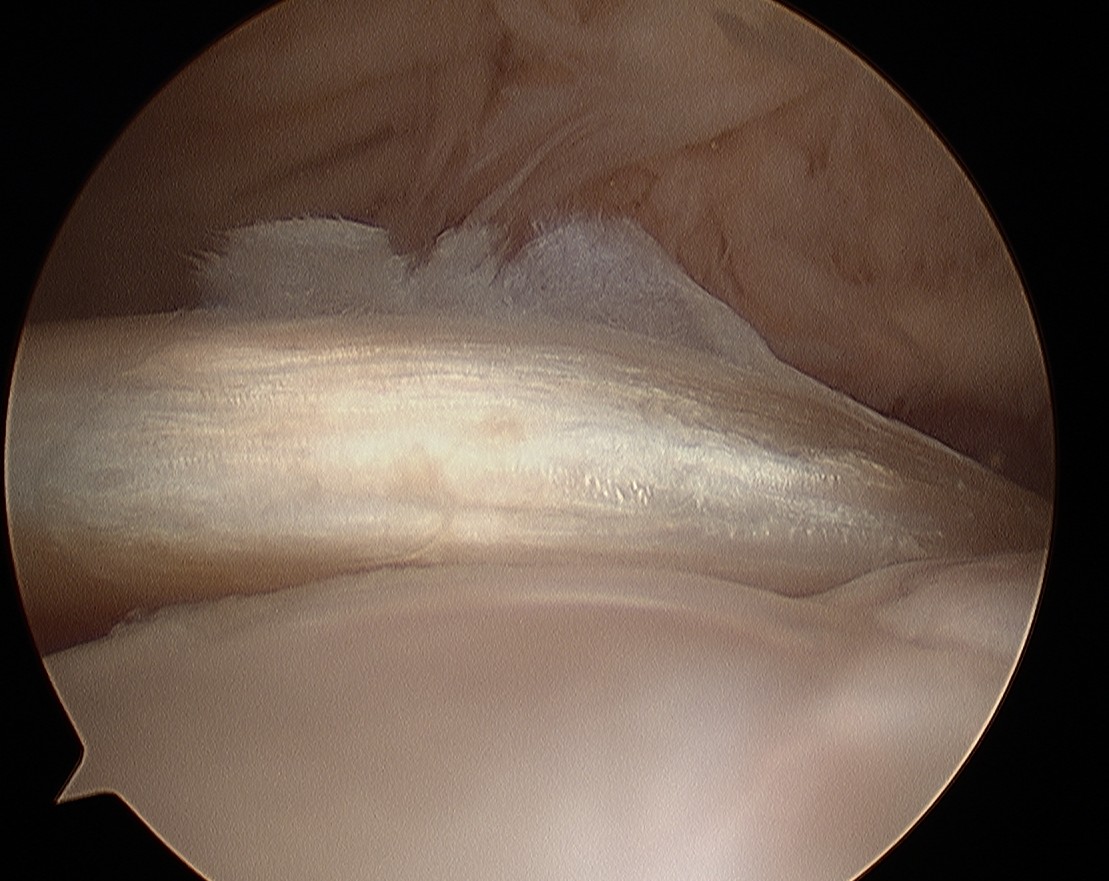

Arthroscopy

Normal

Tendonopathy

Medial subluxation of LHB